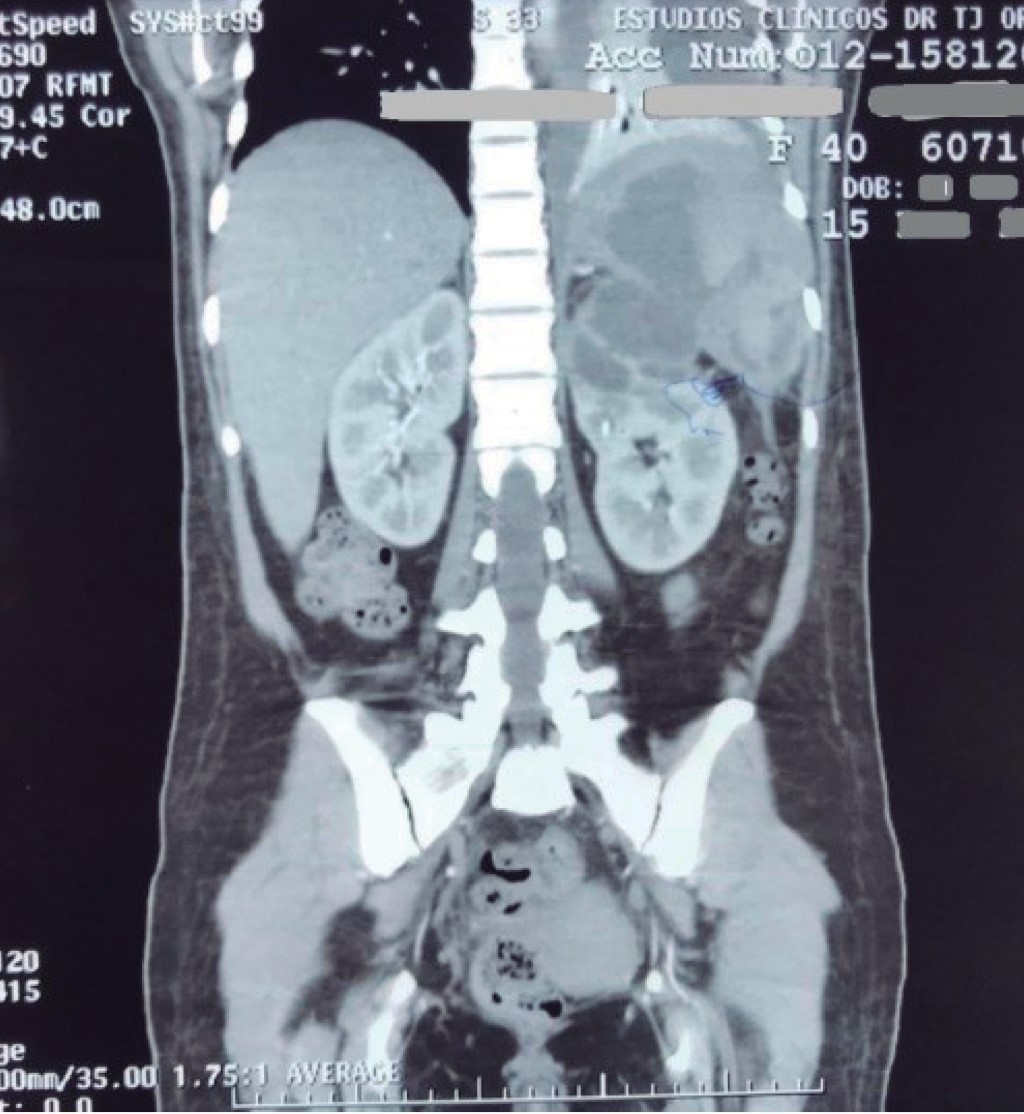

On admission to our hospital, she was conscious; her vital signs showed a blood pressure of 90/60 mmHg, heart rate of 92 beats per minute, respiratory rate of 18 breaths per minute, peripheral oximetry with ambient air saturation of 90%, temperature on admission of 37.6 °C, which during his management in the emergency room averaged 38 °C. The physical examination showed basal hypoventilation of the left lung and pain in the left hypochondrium and epigastrium without peritoneal irritation or muscle resistance. The rest of the physical examination was without alterations or data relevant to the clinical picture. Laboratory tests showed hemoglobin 10.5 mg/dl, hematocrit 29.4%, white blood cells 8,800/µl, neutrophils 78%, lymphocytes 14.8%, fibrinogen 597 mg/dl, alkaline phosphatase 119 IU/l, lactate dehydrogenase 191 IU/L, lipase 117 U/l and C-reactive protein 37.5 mg/l, and creatinine 0.7 mg/dl. The urinalysis showed amber urine with pH 5, leukocyte esterase 500 cells/µl, protein 25 mg/dl, 10-15 erythrocytes per field, leukocytes 25-30/field, and abundant bacteria. A new contrasted abdominal tomography scan showed a 20% left pleural effusion, a kidney with cysts communicating with the spleen, and splenomegaly with abscesses inside (Figure 1). She had clinical deterioration six hours after admission with decreased blood pressure, maintaining mean arterial pressures between 60-70 mmHg, tachycardia with 110 to 120 beats per minute within the average range, diaphoresis, persistent and increased abdominal pain, so it was decided to urgently admit the patient to the operating room to perform an exploratory laparotomy. The left retroperitoneal space was checked with the Cattell-Braasch maneuver, finding an intense perisplenic inflammatory reaction and adhesions between the spleen and left diaphragm, liver, kidney, and retroperitoneal area; the left kidney had a loss of anatomy in the upper pole with abscessed cysts and communicated with the spleen with the presence of an abscess inside (Figures 2 and 3). Splenectomy and en bloc nephrectomy were performed; pus was found inside both pieces and sent to pathology for study, and a Penrose-type drain was placed and directed to the surgical bed. In the histopathological examination, both organs were found adhered with irregular edges, abscessed areas, congestion, and fibrinopurulent material. In conclusion, a left kidney with abscessed acute pyogenic pyelonephritis (renal and splenic pyogenic abscesses) negative for malignancy was found.

Figure 1